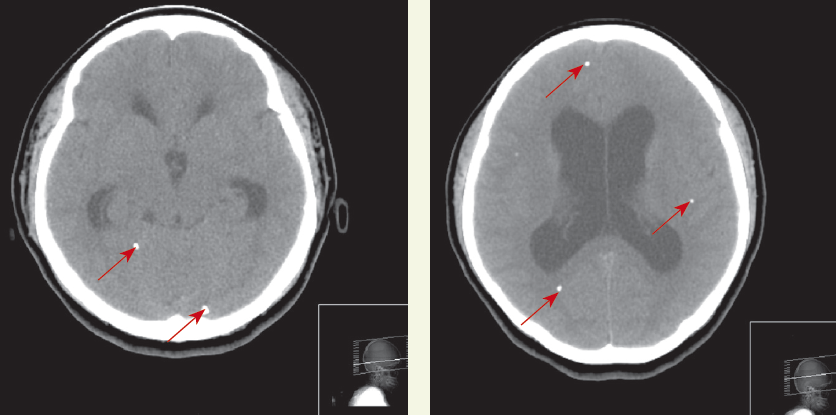

A cranial CT scan showed calcifications (arrows) scattered throughout the brain parenchyma with hydrocephalus. Intravenous ceftriaxone and metronidazole were started; phenytoin was added after seizures developed. Results from blood cultures were negative. The patient underwent a ventriculoperitoneal shunt. Results of cerebrospinal fluid analysis and culture, Cytomegalovirus serology, Toxoplasma serology, and tuberculosis polymerase chain reaction were all negative. Serology for cysticercosis was reactive. Postoperatively, albendazole (800 mg/d) and dexamethasone were started.

Neuroimaging may show a nonenhancing hypodense lesion, variable degrees of edema, calcifications, or hydrocephalus. Conditions that can present with similar features include toxoplasmosis, schistosomiasis, tuberculosis, cytomegalovirus infection, abscess, primary brain and metastatic cancers, trichinosis, and sarcoidosis. Finding a scolex as a mural nodule within the cyst is pathognomonic for neurocysticercosis. The appearance on CT or MRI scans is frequently nonspecific and may be difficult to differentiate from other brain lesions. A definitive diagnosis can be made using proposed diagnostic criteria based on clinical presentation, imaging, serology, and epidemiological data.3